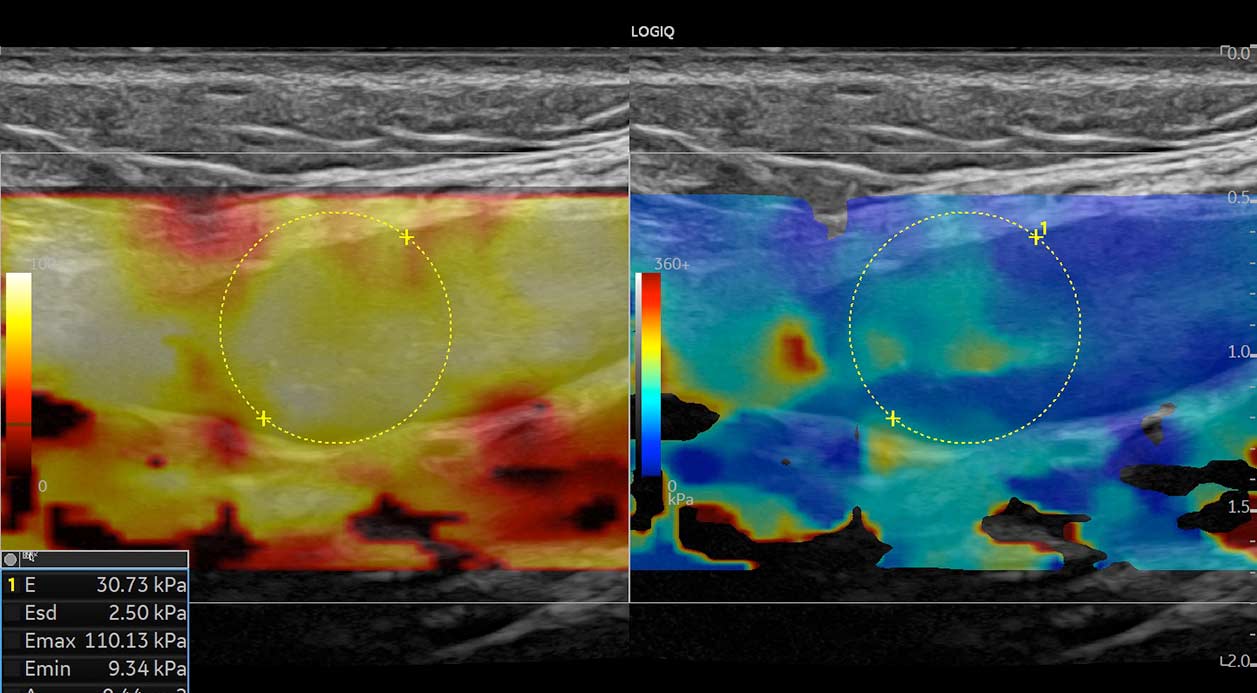

ΕΛΑΣΤΟΓΡΑΦΙΕΣ